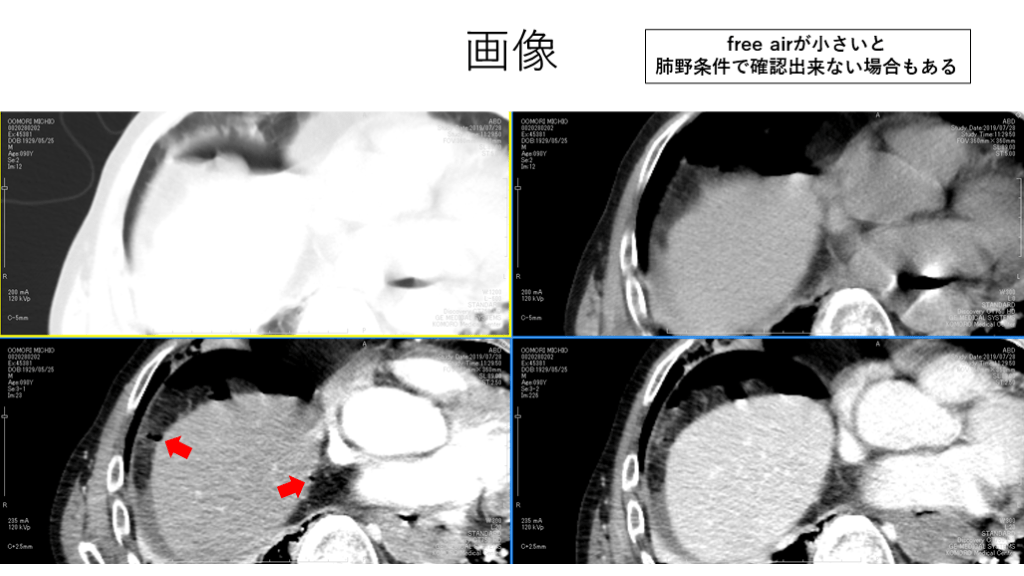

画像 free airが小さいと 肺野条件で確認出来ない場合もある

Take home message ・free airを検索する際には肺野条件と他条件を並行して検索が有用。 ・腹部条件だけだとairを見落とす可能性がある。 ・free airと見分けにくい構造に注意する。他条件との比較が重要。  (例:肺実質、腸管内ガス、濃度の低い脂肪織) ・腸管“内”or“外”を見分けるには根気強く腸管を追うしかない。